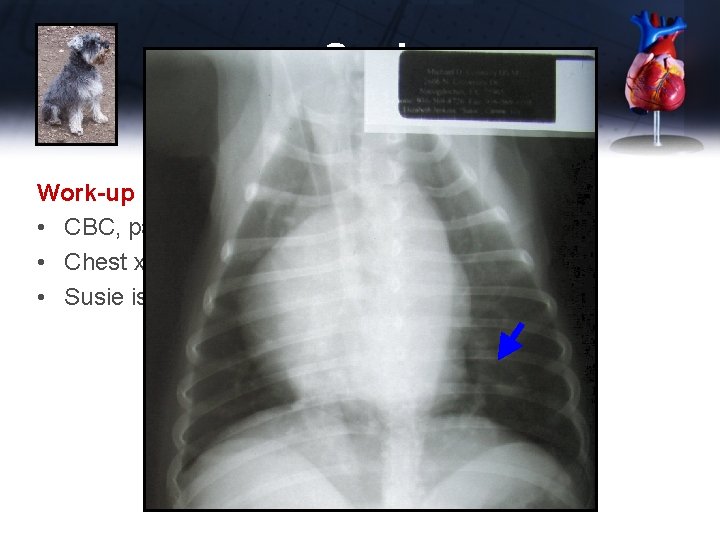

Susie Work-up • CBC, panel, electrolytes, UA normal • Chest x-rays

Susie Work-up • CBC, panel, electrolytes, UA normal • Chest x-rays Vertebral Heart Size = 10. 7 (normal 8. 5 -10. 5) Enlarged main pulmonary artery

Susie Work-up • CBC, panel, electrolytes, UA normal • Chest x-rays • Susie is not on heartworm prevention